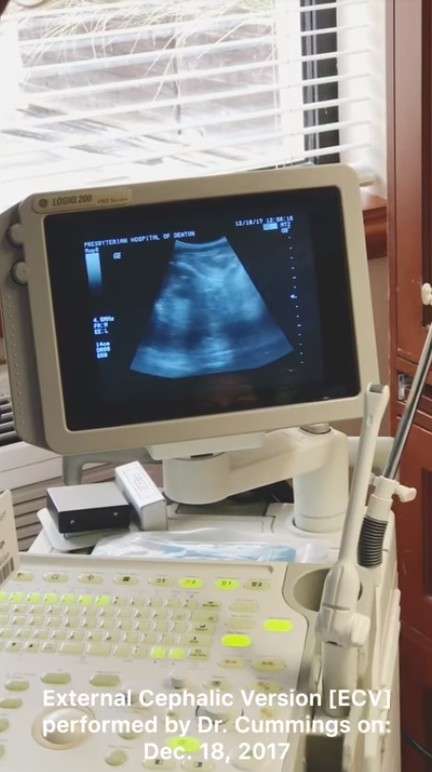

影片中可以看到醫生正在努力的使用ECV,嘗試讓子宮中的嬰兒轉正。

經過一段時間的努力,超音波熒幕上的嬰兒終於顯示順利轉正了,讓躺在病床上的媽媽也露出了欣慰的笑容。